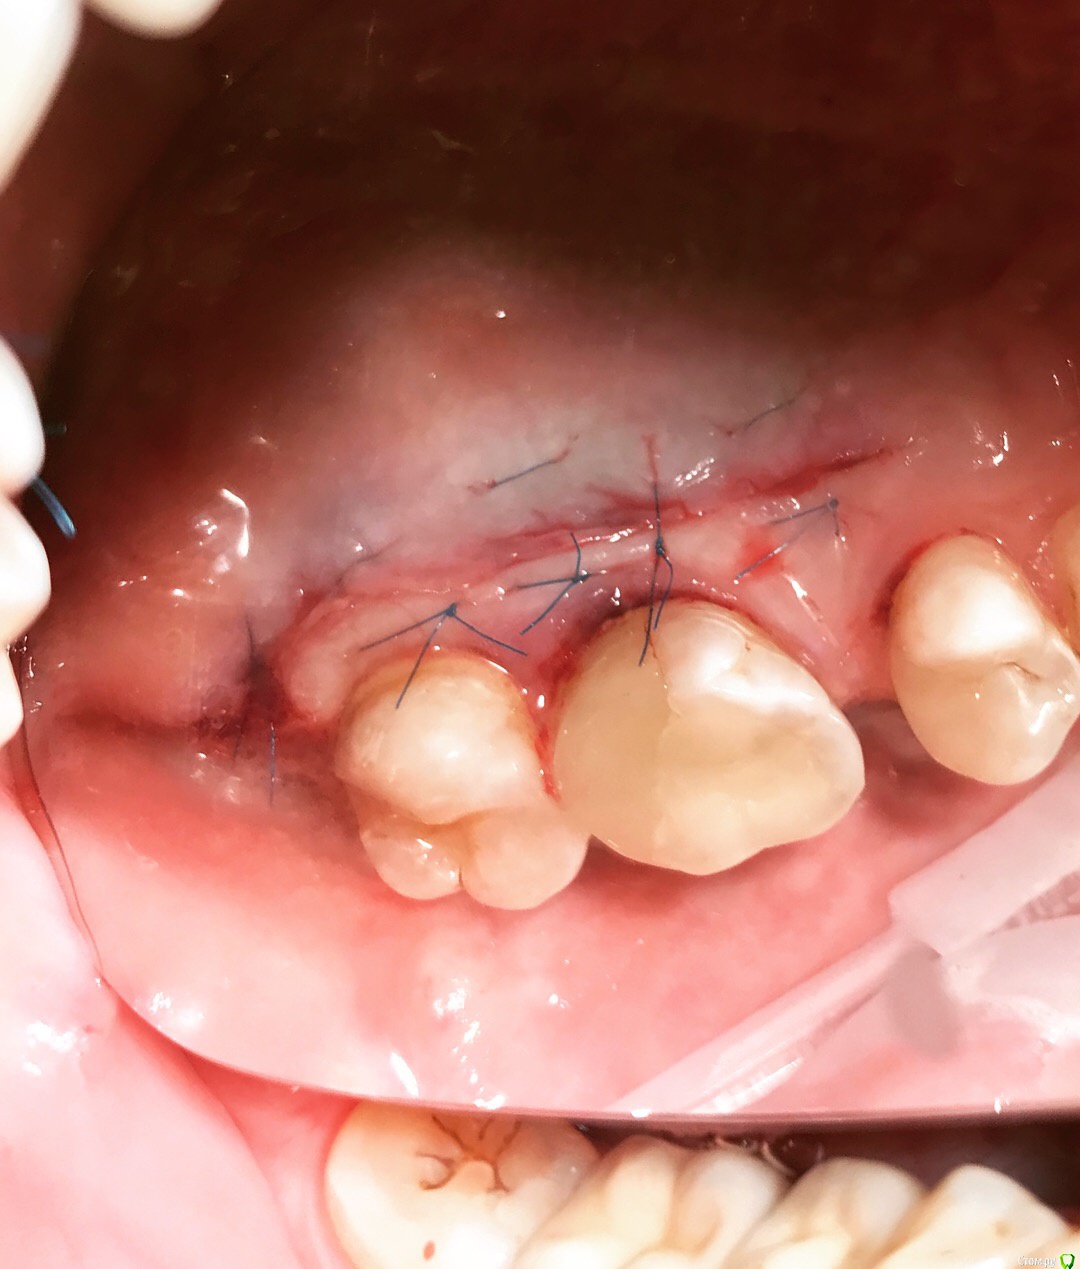

Santi Опубликовано 12 сентября, 2018 Поделиться Опубликовано 12 сентября, 2018 Коллеги, интересно мнение как бы вы поступили в аналогичной ситуации) Имеем Область забора и полученный ССТ Сразу после 2,5 мес пост оп 9 Ссылка на комментарий